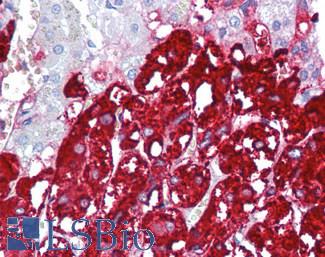

Estrogen Receptor / ESR1

Anti-ER Alpha / Estrogen Receptor antibody IHC staining of human breast. Immunohistochemistry of formalin-fixed, paraffin-embedded tissue after heat-induced antigen retrieval. Antibody LS-B10527 dilution 1:100.